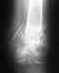

1 апреля 2006 года в ДТП получены много оскольчатые переломы голени на одной ноге и бедра на другой. Установлены аппараты Илизарова. На голени убирали дистракцию, а на бедре транформацию кости (меняли угол кайками в течение месяца). Сейчас сказали, что можно давать нагрузку на обе ноги, но мешают сильные боли. Как правильно организовать процесс стояния и обучения ходьбе на обеих смоманных ногах? Нужны ли занития ЛФК? Какие?